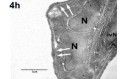

Die chemokininduzierte Einwanderung neutrophiler Granulozyten in die Lunge ist ein zentraler pathophysiologischer Mechanismus im Rahmen des akuten Lungenversagens. Die zentrale Bedeutung von DARC für die Konzentration zirkulierender Chemokine impliziert eine mögliche Rolle bei der Entstehung des akuten Lungenversagens.

Dieses Projekt soll die Bedeutung von DARC im ARDS charakterisieren.